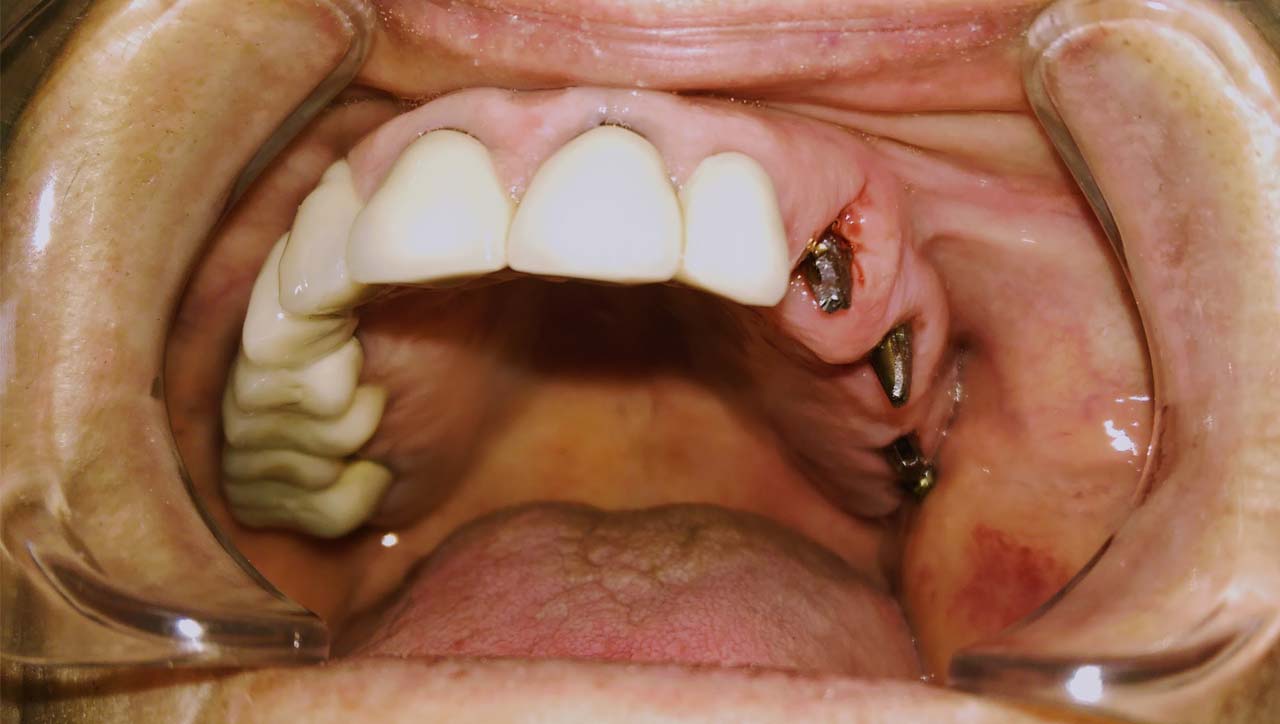

Elhanyagolt fogsor cseréje 2 nap alatt

2 nap alatt varázsoltuk ezt a szép esztétikus alsó, felső körhídat implantátumokkal megtámasztva a korábban elhanyagolt szájba. Az 1. nap 26 fogat távolítottunk el, mert annyira rossz állapotban voltak, és rögtön azonnal terhelhető IHDE svájci implantátumokat raktunk be, fentre 8, lentre 6 darabot. A sebeket összevarrtuk és intraorális szkennerrel digitális lenyomatot vettünk. 2 nap múlva pedig beragasztottuk a kész PMMA műanyag körhidakat. Dr. Kelemen Péter és a Symbion Fogtechnika munkája.